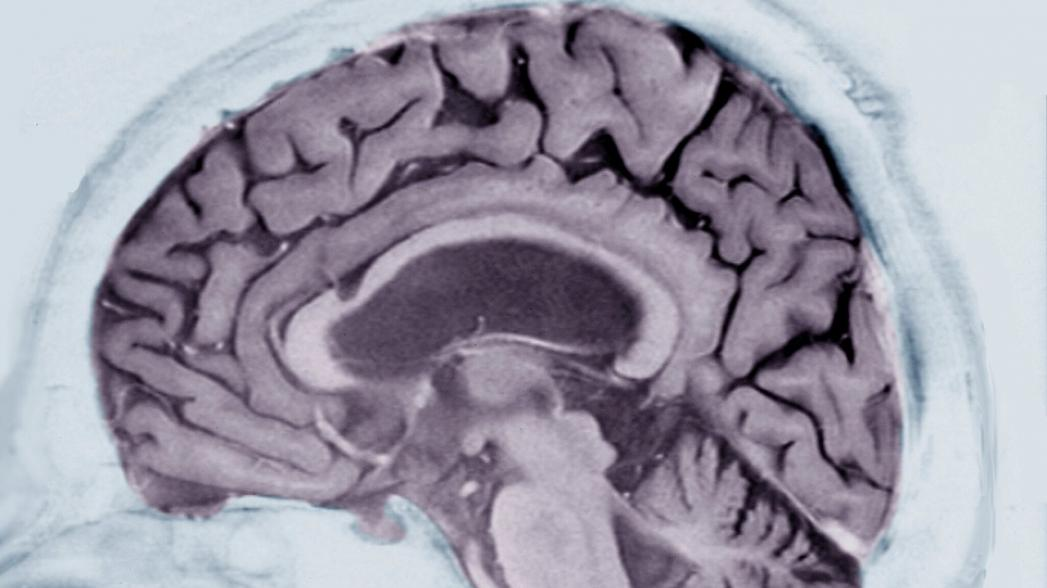

Новый алгоритм искусственного интеллекта, созданный IBM, может помочь врачам диагностировать или предсказывать наступление болезни Альцгеймера - за годы до появления симптомов.

И все, что нужно, это чтобы субъект рассказал алгоритму историю. Сравнивая образцы текста, написанные участниками исследования в течение нескольких лет, алгоритм смог предсказать наступление болезни Альцгеймера на годы вперед с 75-процентной точностью. Потенциально это решение дает врачам новый инструмент для выявления болезни Альцгеймера и других серьезных нейродегенеративных состояний до того, как их признаки станут проявляться.

Алгоритм рассматривает данные неврологического исследования, в котором приняли участие 270 человек, которым, помимо прочего, было предложено наглядно описать то, что происходило на простой картинке несколько раз в течение нескольких лет. Основываясь только на этих образцах, алгоритм научился распознавать такие закономерности, как все более повторяющиеся фразы, опечатки или недостающие слова, как признаки нейродегенеративного заболевания.